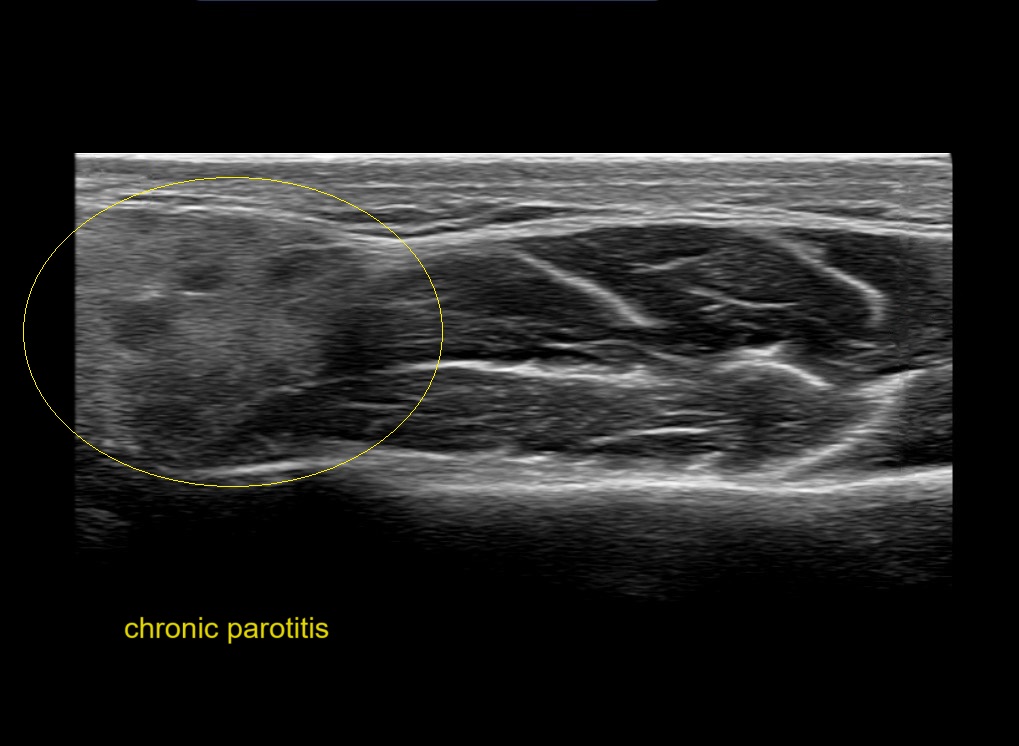

Filler injections in the parotid gland may go unnoticed, however, inflammatory reactions and abscesses may occur. Hypervascularity can be seen with color doppler. Filler deposits are supposed to be injected into the superficial fatty layer . The space to inject into this layer may be limited. Routinely we measure a width of 2-4 millimeters with sometimes subcutaneous layers being less than one millimeter thick.

Study the first image to recognize the different layers. If you are sure about the layers, swipe to the second image to view the answer (if applicable).